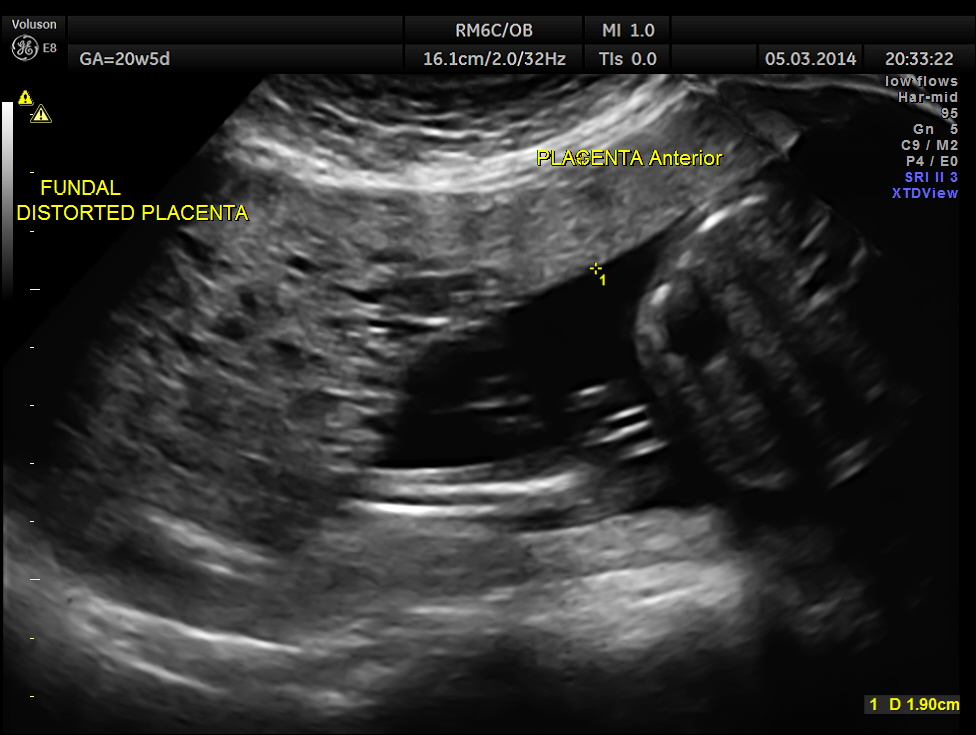

The placenta was on the anterior wall and the scan showed a distinct mass lesion in the antero right lateral portion. The placenta had multiple small cystic appearance in the right lateral aspect . Colour doppler showed no increased vascularity.

Cord insertion seems to be at the junction of the normal and abnormal regions.